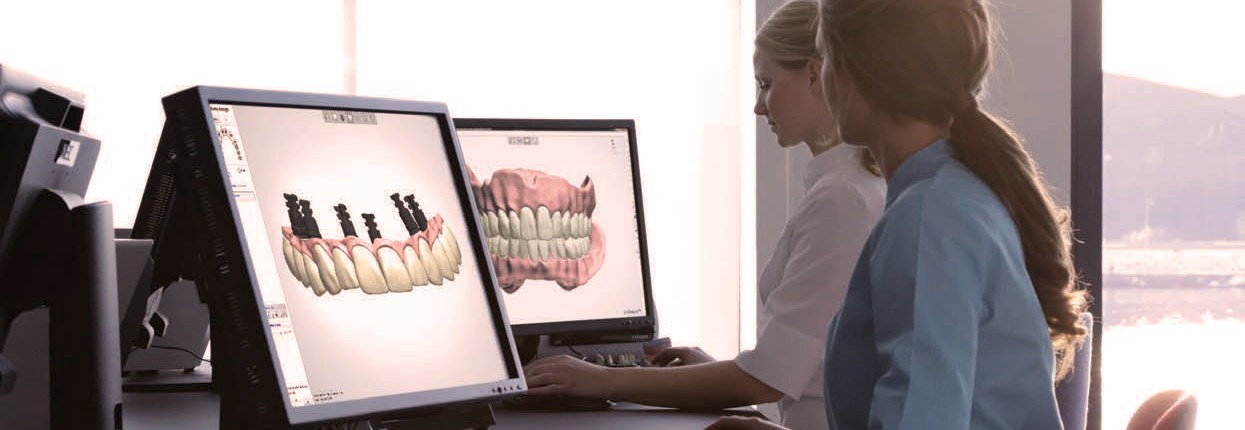

D ESDE PROCAD DISEÑO DENTAL, apostamos por la innovación, punto importante para estar a la vanguardia del mercado, apoyados por el desarrollo de recursos tecnológicos y humanos haciendo frente a las demandas que hoy por hoy se nos exigen.

PROCAD DISEÑO DENTAL Como empresa dinámica y en constante evolución, nuestra meta es sobrepasar los límites de la odontología digital y proporcionar a nuestros clientes soluciones sólidas y fáciles de usar, para un mercado en rápida evolución